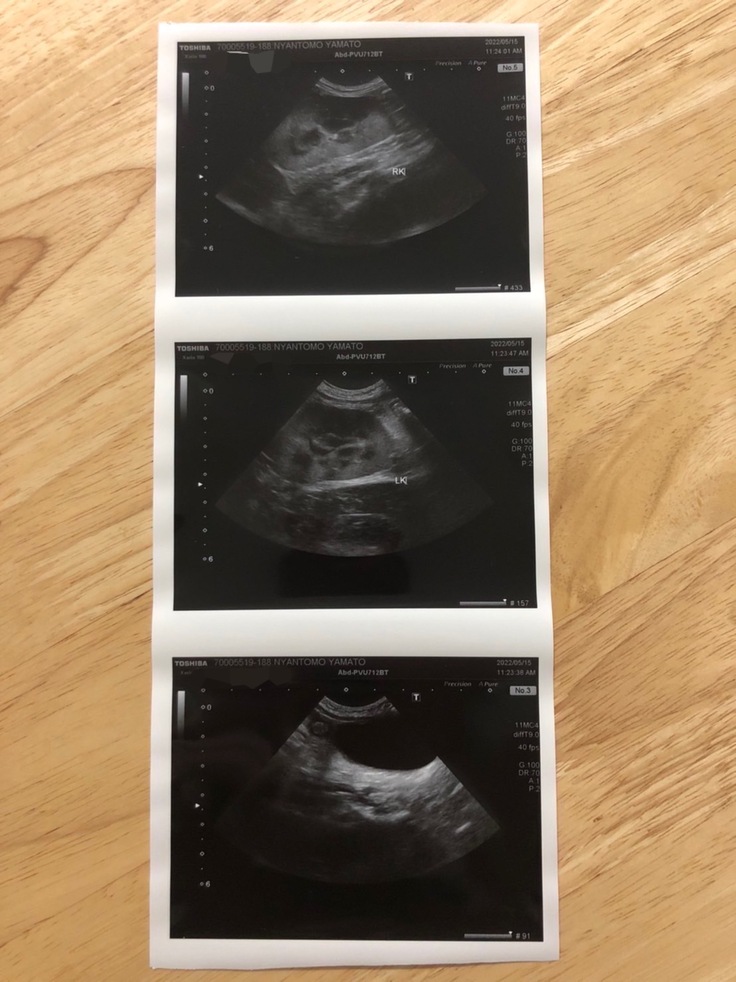

(エコーの結果。腹部エコーの黒い部分が腹水)

(エコー検査画像)